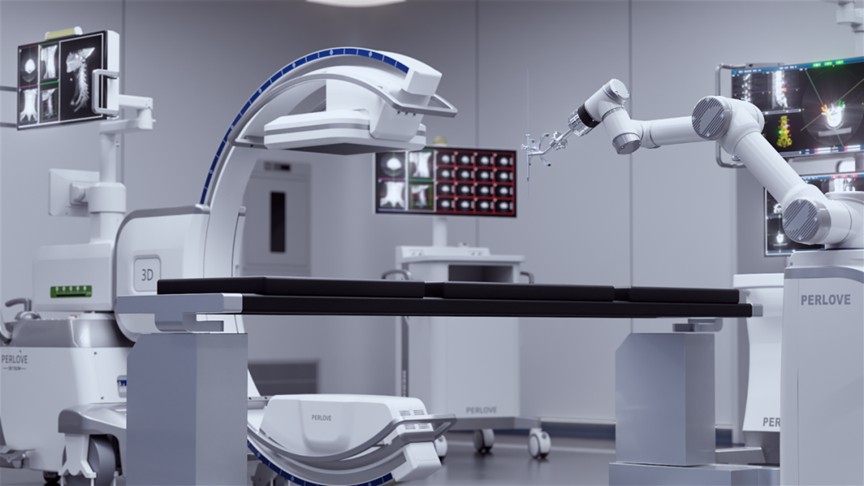

During the surgery, the medical team used the Perlove Medical’s flat-panel 3D C-arm to acquire 3D and CT-like images of the patient, enabling comprehensive visualization of the pedicles. Guided by the robot's 3D planning system, the surgeon mapped each screw's ideal path and angle to achieve maximum screw purchase strength and improve spinal stability by accommodating the unique biomechanical properties of pediatric bone tissue.

One-time planning for quadruple K-wire insertion

The robotic arm enhanced stabilization of surgical instruments, enabling precise execution. Guided by pre-planned trajectories, the system achieved accurate single-attempt pedicle screw placement within narrow vertebral pedicles - effectively navigating the 'anatomical labyrinth'. This approach eliminated risks associated with repeated positioning attempts. The fully integrated system demonstrated perfect coordination, successfully completing the implantation of four pedicle screws with sub-millimeter accuracy.

Fluoro-verified precise K-wire insertion

Fluoro-verified precise screw implantation